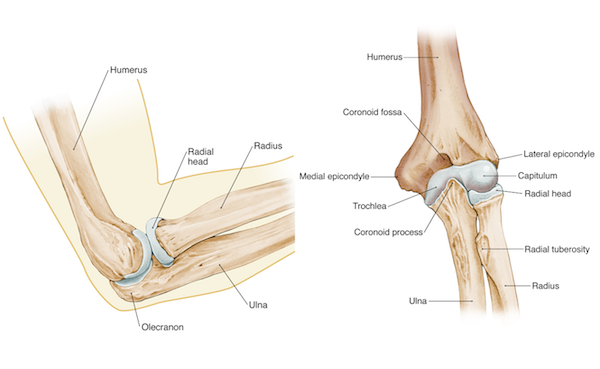

Elbow Arm Anatomy

Elbow Anatomy Full Easy Review OrthoFixar 2025

Elbow Joint Anatomy Movement Muscle involvement

The Elbow Joint Anatomy and 3D Illustrations